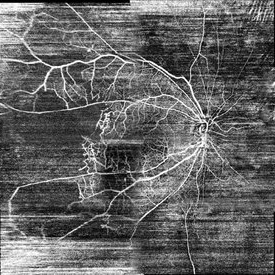

Matrix fundus photograph of 52-year-old woman with proliferative diabetic retinopathy on her both eyes. She had a diabetic history for 19 years. Doctor suggests her to have a vitrectomy on her right eye (poor prognosis).

Photographer: Yohanes Harry Purwanto, Klinik Mata Nusantara

Imaging device: Topcon TRC 50 DX Type IA

Condition/keywords: proliferative diabetic retinopathy (PDR)